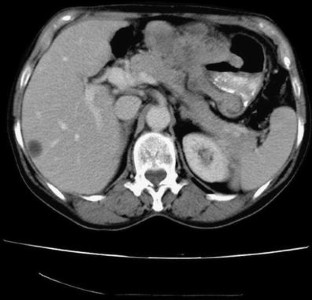

We report a Spanish female who consulted because of fatigue, anorexia, and weight loss. In laboratory data, she presented anemia and markedly elevation of AFP. On CT scan, a gastric mass resulted without hepatic dissemination, and subsequently, gastroduodenoscopy was performed for histological diagnosis. Then, an ulcerated mass was detected and sample was taken, resulting in poorly-differentiated adenocarcinoma of stomach with hepatoid tissue foci, with intense positivity for AFP-immunohistochemical staining. This rare cancer has poor prognosis even with early gastrectomy and chemotherapy.

Fig. 2